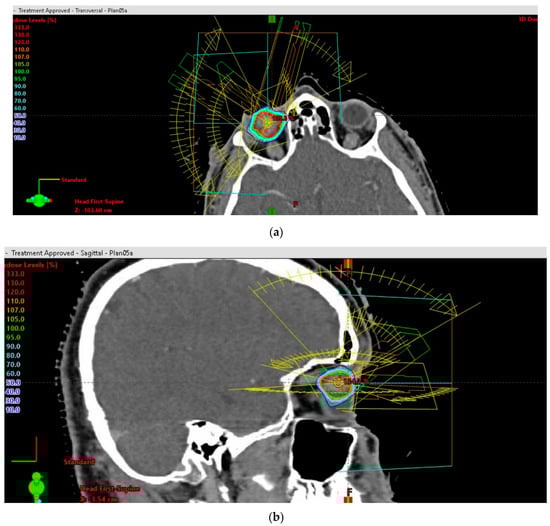

One of the most important quality parameters of the radiation plans was the protection of the optical axis, optic nerve and macula (Figure 4a). The mean gross tumor target volume (GTV) was 1.19 mL (0.40–2.94 mL), and the mean tumor thickness (TT) was 11.15 mm (8.0–15.50 mm). The largest basal diameter (LBD) measured was 15.11 mm in mean (range: 7.6–21.90 mm), and the mean small basal diameter (SBD) was 13.58 mm (range: 6.31–20.40 mm). In 33 patients (66.0%), the tumor was located both in front of and behind the equator. Fifteen patients (30.0%) showed tumor growth within 1–3 mm close to the optic disc. In addition, in 15 patients the tumor extended to the ciliary body (CB), with a gross infiltration of less than 25%. Retinal detachment in two or more quadrants was present in 25 patients, and in only one quadrant in 15 patients. All patients (100%) fulfilled the COMS original criteria, and 92% met the classic COMS (Collaborative Ocular Melanoma Study) criteria for large uveal melanomas [17,18].

The maximum dose gradient (DG) toward the most critical normal tissue between isodose D100% and isodose D50% was 1.5 mm on transverse planes and 1.2 mm on coronal planes. The achievable DG between isodose D100% and isodose D70% towards the most critical structure at risk was 0.75 mm. For central tumors, the actually achieved gradients between D100% and D50% toward the optic nerve were in mean 1.7 mm (95% CI: 1.5 mm–2.0 mm). The actually achieved gradients toward the lids, if they were close to the planning target volume, were 1.7 mm. In patients with tumors close to the optic nerve (0.7–3.0 mm), the distances between the GTV and the optic nerve were quantified (Figure 4a and Figure 5).

The prescription dose D99.5% for the PTV ranged from 19.01–25.01 Gy, mean 22.12 Gy. The mean dose to the PTV over all patients was 26.67 Gy (24.72–30.53). The mean number of selected arcs amounted to 5 (4–12), all arranged with minimized brain entrance or exit fields (Figure S2). The mean brain dose was only 0.14 Gy (0.04–0.26 Gy). The radiation dose to the 1cc of brain with the highest dose exposure was in mean 1.7 Gy (0.65–2.8). The ratio (R50%) between the 50% isodose volume (PIV50%) [7.55 mL (2.70–16.00)] and the PTV was in mean 3.12 (range: 2.00–5.00), and the mean ratio between the ESD of the PIV50% and the ESD of the PTV was 1.457 (range: 1.27–1.70) on average. The ratio of the ESD of the PIV100% to the ESD of the PTV averaged 0.962 (0.89–1.10). The mean conformity index (CI) was 1.2 (1.09–1.55); the mean gradient index (GI) amounted to 2.6 (2.35–3.38). The mean dose-gradient index (DGI) for an equivalent sphere equaled 121.20 (120.00–122.64). The real DGI for the irregular target volume amounted to 95.86 (84.5–110.01) (Figure 4b).